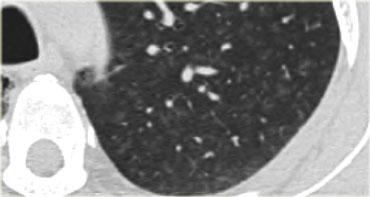

Hình bên trái là một trường hợp bệnh bụi phổi silic cho thấy các nốt có kích thước khác nhau với phân bố ngẫu nhiên và dưới màng phổi.

Một nốt có chứa vôi hóa (mũi tên).

Lưu ý sự vắng mặt của kiểu phân bố theo đường bạch huyết (quanh phế quản-mạch máu và dọc theo các khe liên thùy), vốn là gợi ý của bệnh sarcoidosis.

Cùng bệnh nhân bụi phổi silic như các hình trước, cho thấy một khối tập hợp ở vị trí cạnh rốn phổi thuộc thùy trên phổi phải. Thùy trái cho thấy nhiều nốt có kích thước khác nhau.